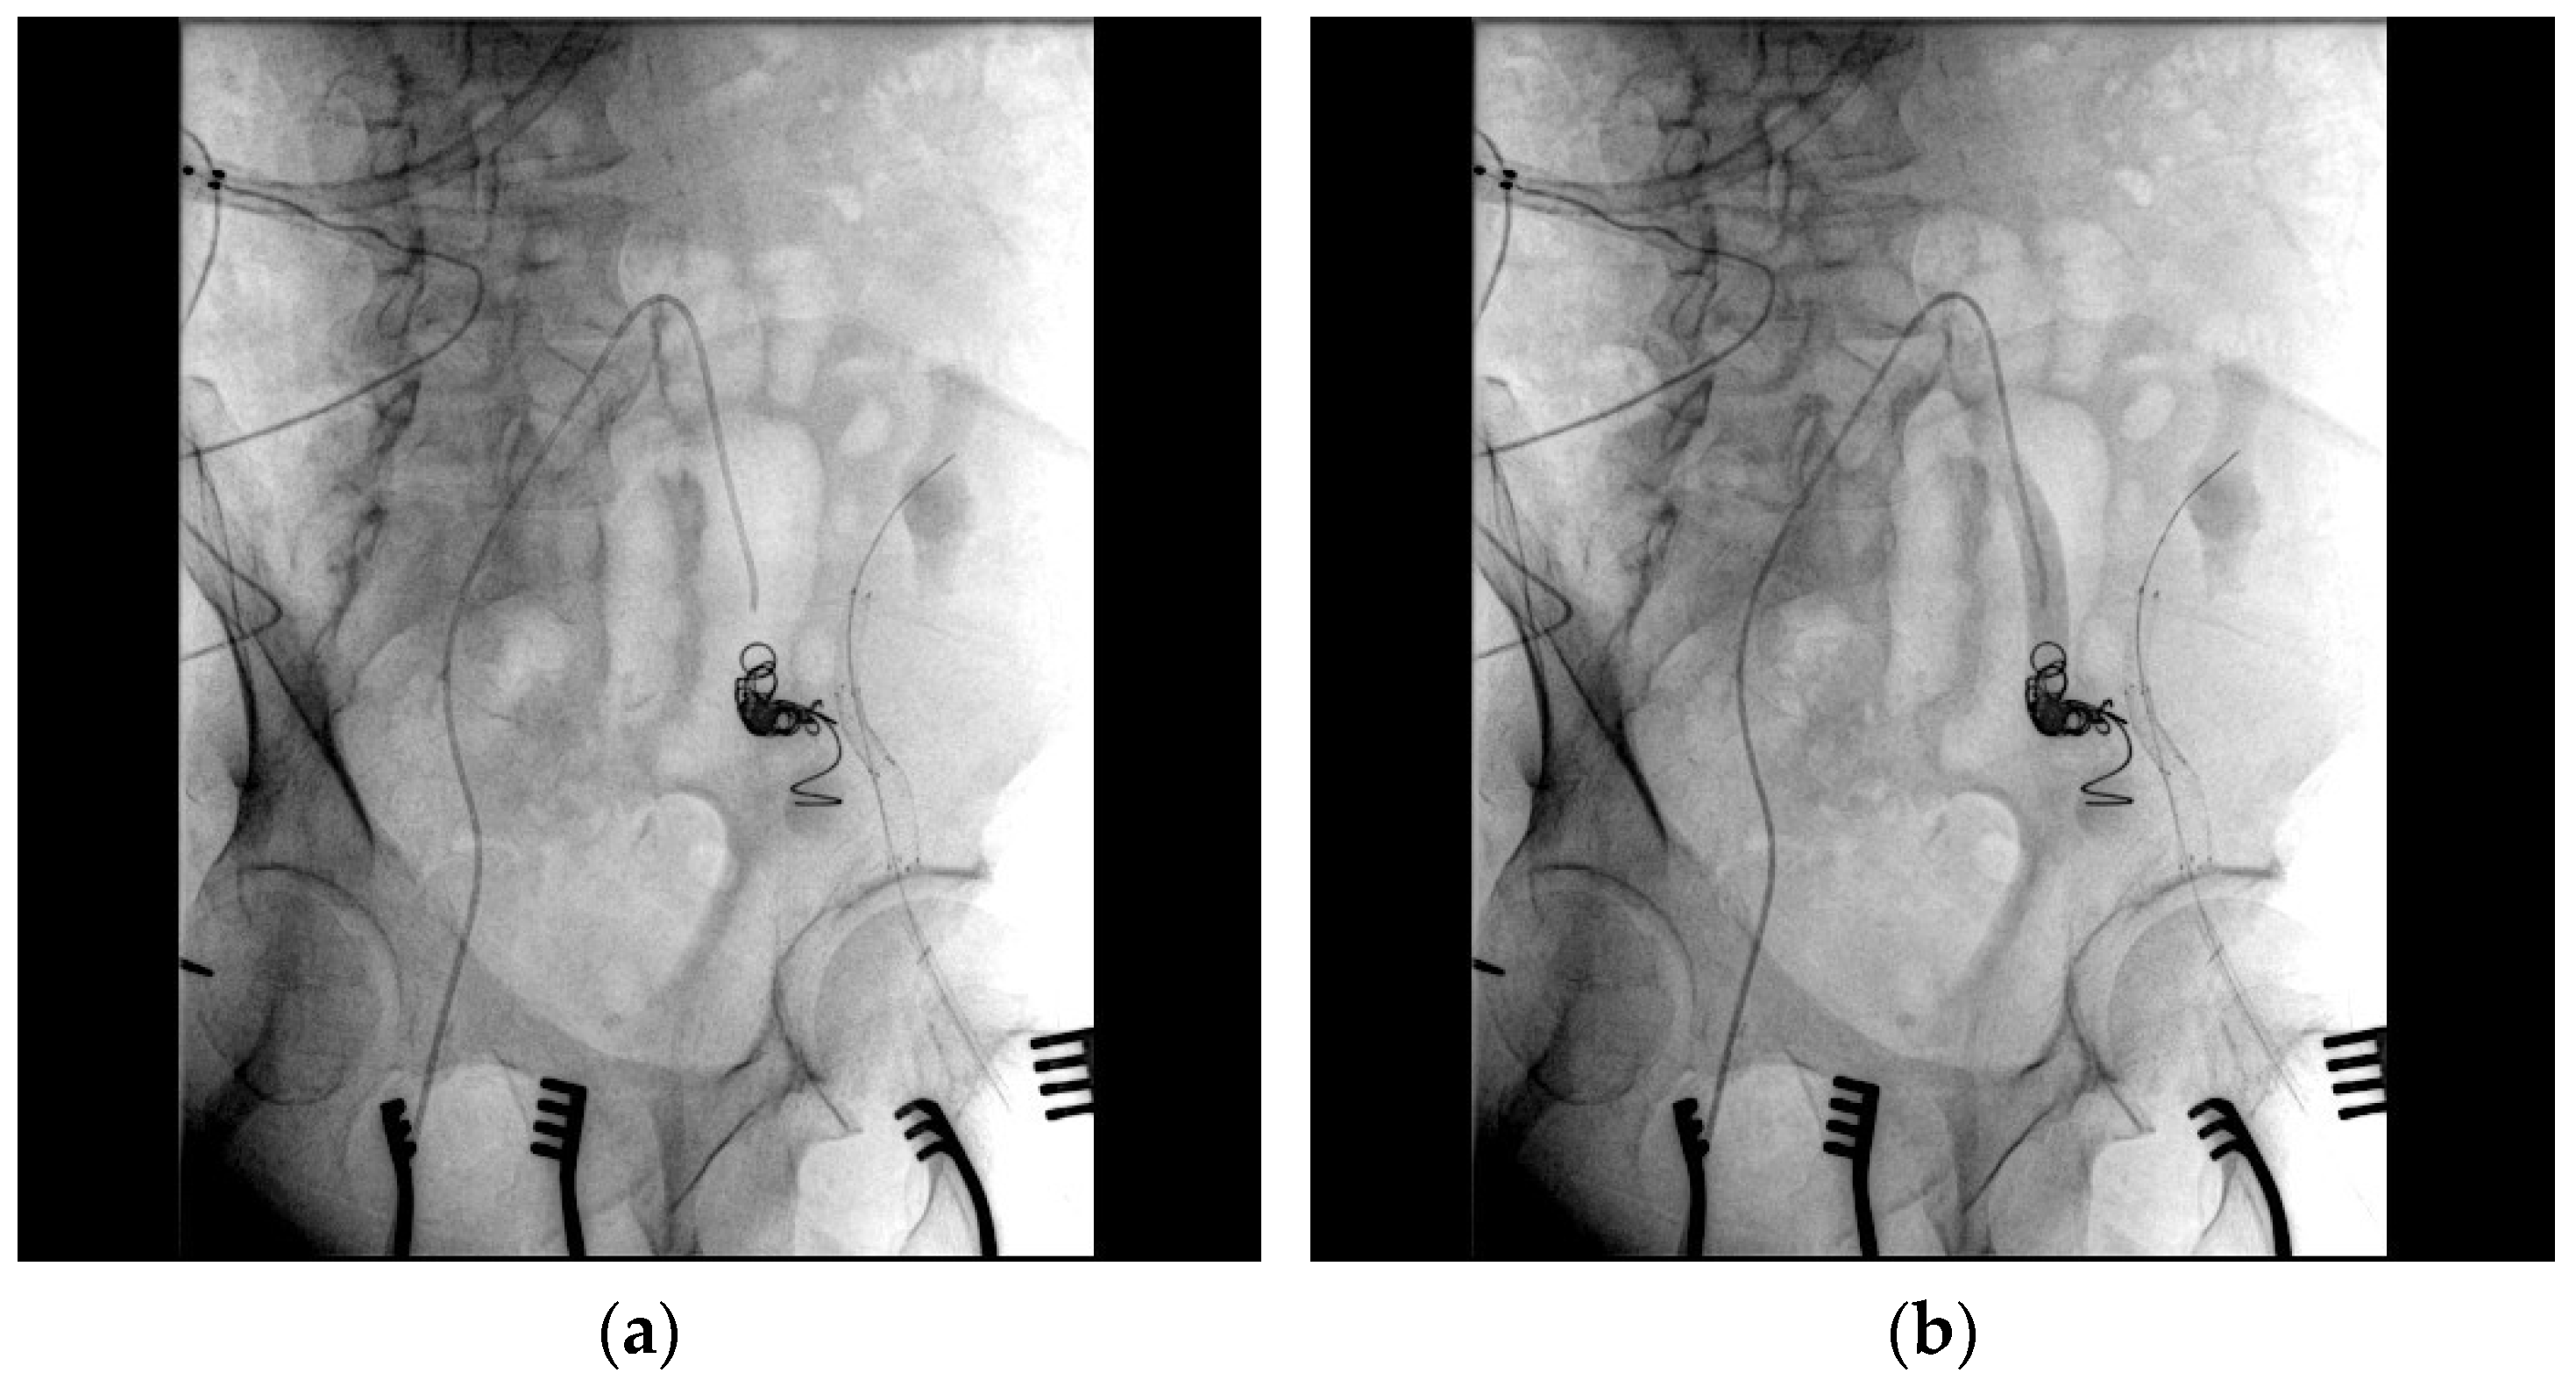

- Bypass grafting ensured continuous perfusion to the lower limb, mitigating the risk of ischemic complications;

- Endovascular stenting minimized surgical trauma while effectively excluding the pseudoaneurysm;

- Coil embolization provided an additional layer of pseudoaneurysm isolation, further enhancing treatment efficacy.